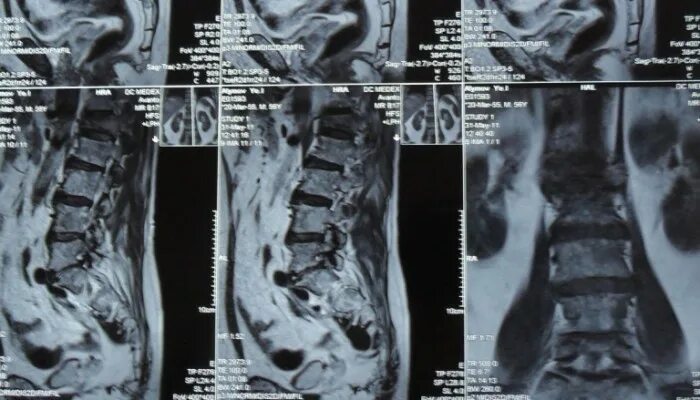

Метастазы в поясничном отделе симптомы